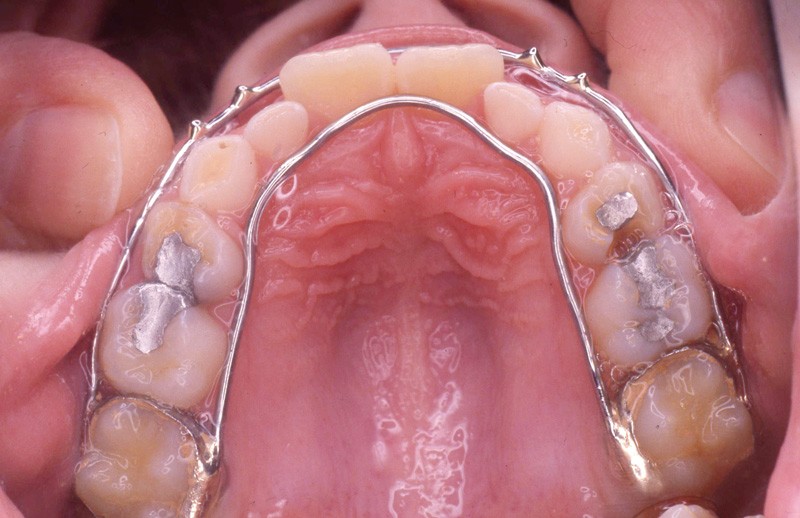

L’examen de la denture (fig. 3 à 5) montre :

• dans le sens transversal, une endomaxillie bilatérale prédominante dans la région canine.

Pendant cette première étape de traitement, les tractions postéro-antérieures sont portées la nuit, soit 8 à 9 h /24 h, sur masque de Delaire pendant 13 mois, avec des tractions d’environ 800 g (fig. 7 à 9).